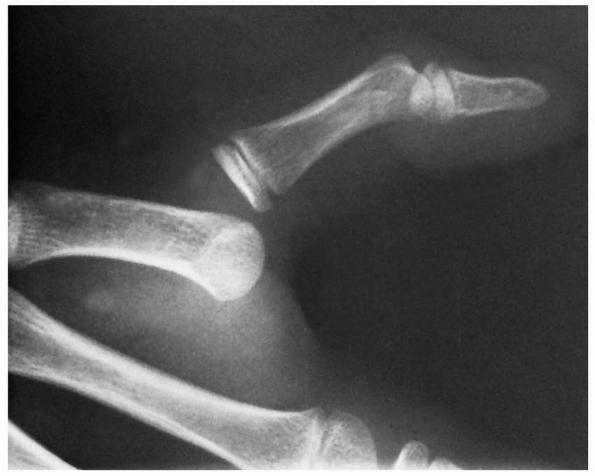

forced extension of the flexed DIP joint. This mechanism can result in

either a bony avulsion injury or a soft tissue disruption of the flexor

digitorum profundus (jersey finger) (Fig. 8-13).106,205

An avulsion fracture often limits flexor digitorum profundus retraction

in the pulley system by tethering of the bone fragment on the A5 or A4

pulley. The radiographic location of the bony fragment identifies the

level of tendon retraction. In contrast, soft tissue disruption of the

flexor digitorum profundus frequently retracts into the palm. Diagnosis

of this injury is often missed in the acute setting.